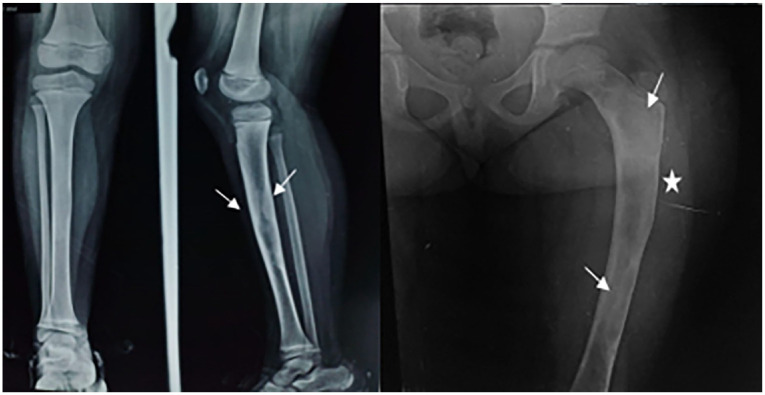

纤维发育不良是一种罕见的非遗传性先天性疾病,主要有两种形式:单相和多相。单恒定型较为常见,而多恒定型通常伴有综合征,较为罕见。本病例涉及一名 10 岁的患者,他被诊断为多发性纤维发育不良并伴有内分泌病。本报告根据患者的病例,从临床和放射学方面探讨了这种疾病。

Fibrous dysplasia is a rare non-hereditary congenital condition characterized by 2 main forms: monostotic and polyostotic. Monostotic is the more common form, while polyostotic, often associated with a syndrome, is rarer. The case presented involves a 10-year-old patient who was diagnosed with polyostotic fibrous dysplasia accompanied by an endocrinopathy. This report explores the clinical and radiological aspects of this condition based on the patient's case.